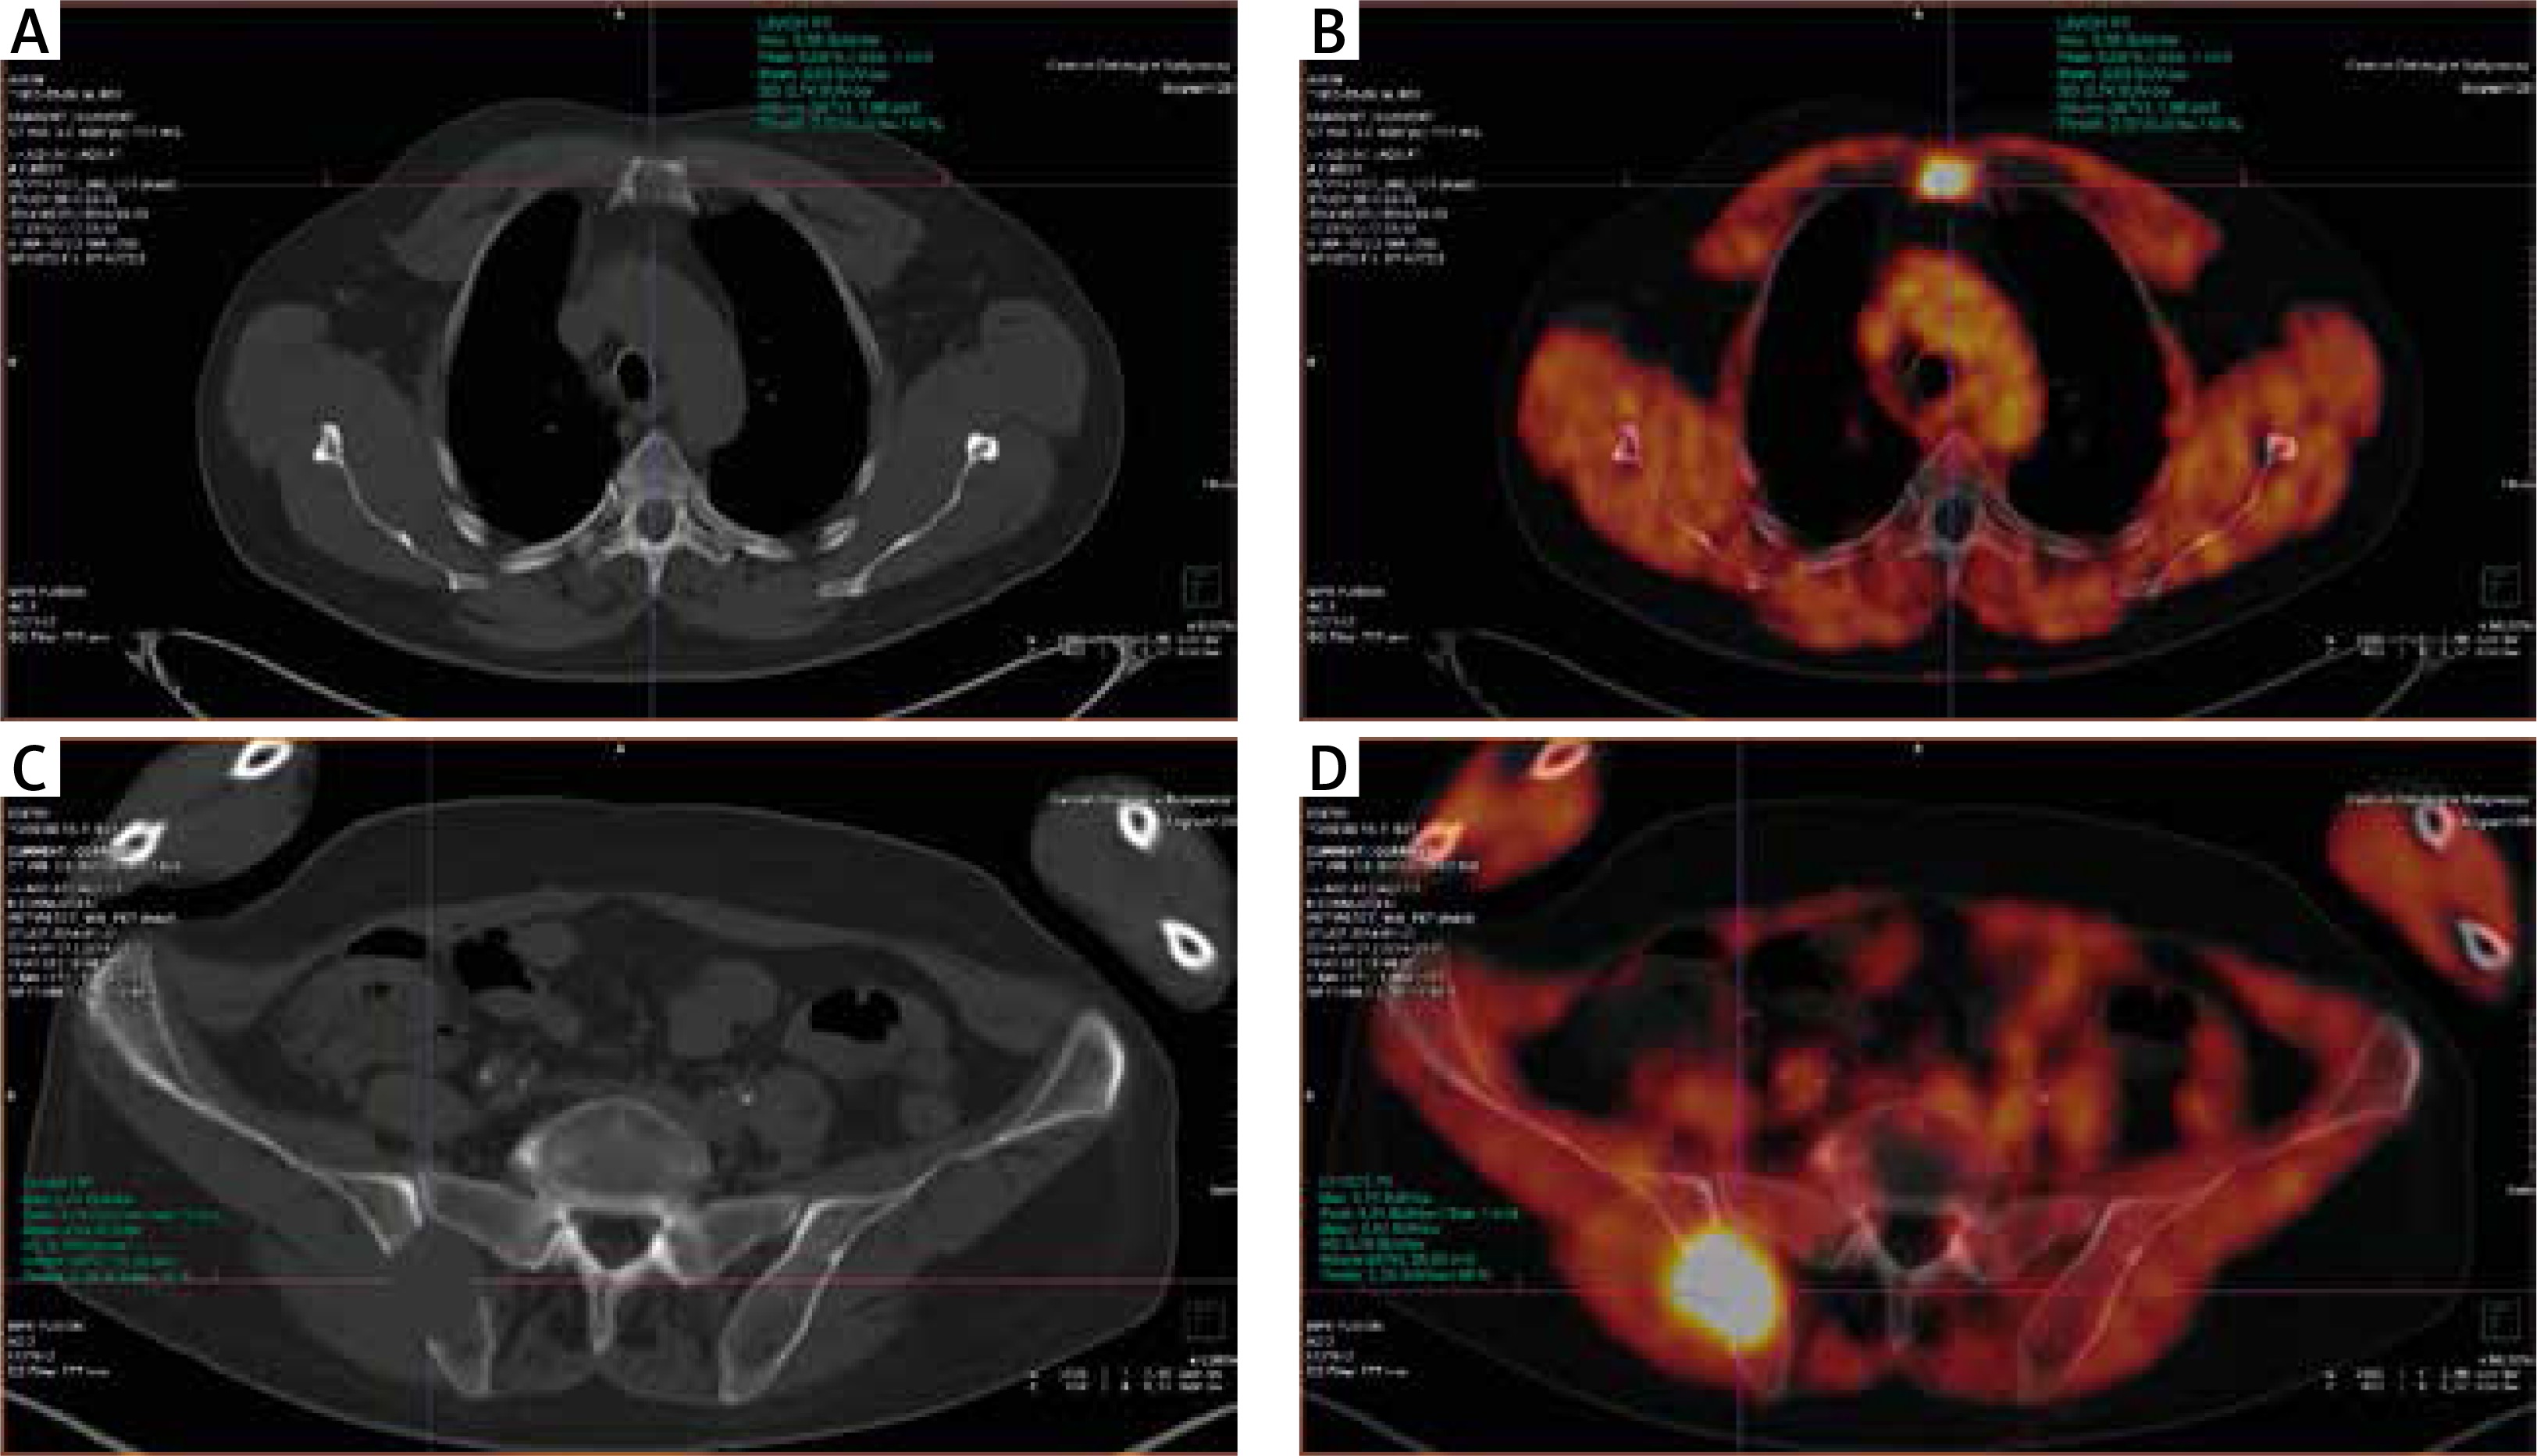

Fig. 1

Patient no. 12, newly diagnosed multiple myeloma before the treatment. A) Computed tomography – lytic lesion localised in the sternum. B) The same lesion on 18F-FET PET/CT fusion image with high FET uptake (converted to black and white). C) Computed tomography – lytic lesion localised in the right iliac crest. D) 18F-FET PET/CT fusion image with high FET uptake in iliac crest

Fig. 2

The same patient after completion of therapy. A) Computed tomography (CT) – lytic lesions localised in the sternum – no difference to the status before therapy. B) 18F-FET PET/CT, fusion image with low FET uptake in the lytic lesion visible on CT in sternum. C) Computed tomography – lytic lesion localised in the right iliac crest – no difference to the status before therapy. D) 18F-FET PET/CT fusion image with low FET uptake in iliac crest